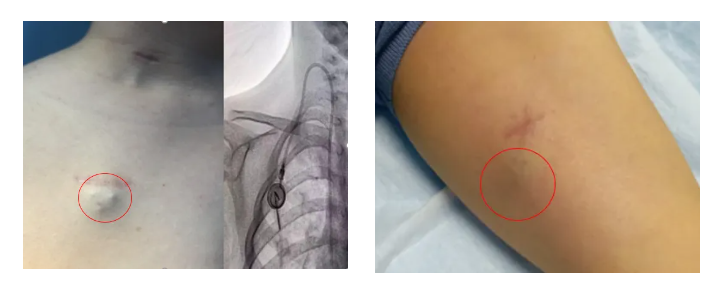

輸液港,即完全植入式輸液港(PORT),是一種可完全植入皮下并長期留存體內的輸液裝置,主要由注射座(又稱港體)和硅膠導管兩部分組成。注射座被埋植于胸部皮下,導管則連接到上腔靜脈,形成一個閉合的靜脈輸液系統(tǒng)。其常見類型有手臂輸液港與胸壁輸液港。

提高生活質量:輸液港埋植體內,外觀無外漏導管,患者可自由活動。